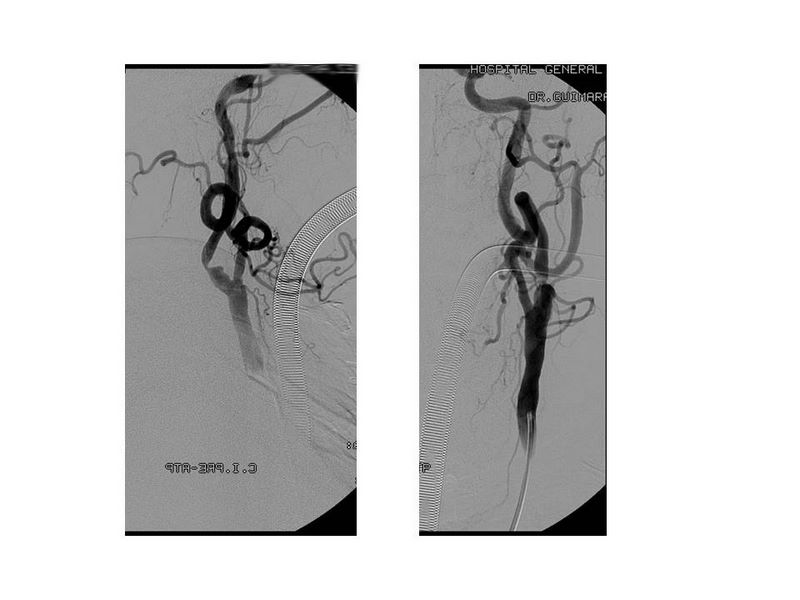

Otro Stent Carotideo